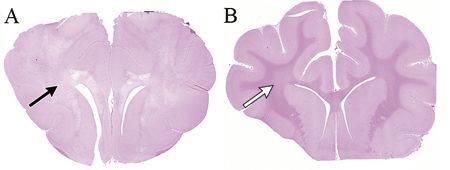

Establishing a definitive diagnosis of intoxication is difficult. Frequently, a definitive diagnosis is made by postmortem examination of the CNS. Grossly, the brain and spinal cord often appear normal, but foramen magnum herniation of the cerebellar may be observed (Figure 1). Microscopically there is widespread spongy degeneration (vacuolation) of the CNS white matter (Figure 2).3,5-7 Definitive proof of intoxication requires measurement of bromethalin/desmethylbromathelin tissue concentrations.

Figure 1. (A) Subgross, transverse section of the cerebrum of a cat with bromethalin intoxication. Note the loss of staining of the white matter (black arrow). (B) Subgross transverse section of the cerebrum of a normal cat brain at approximately the same level as in (A). The white matter is easily identified based on its staining (white arrow). Hematoxylin and eosin staining. Image courtesy of Drs. Marc Kent and Eric Glass.